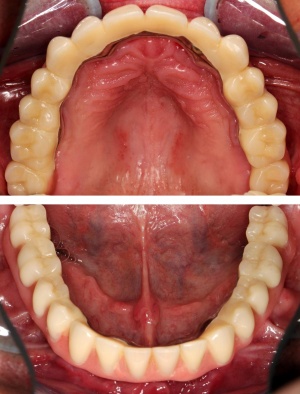

Nach Genehmigung des Antrages erfolgte im März 2012 die Extraktion aller Zähne (Abb. 1).

Im August 2012 erfolgten die 3D-gestützte Implantation (6 Implantate, Firma Nobel Biocare, System Active) im Oberkiefer mit Bone Split sowie eine An- und Auflagerungsosteoplastik vom linken Beckenkamm im Unterkiefer nach Entfernung der Miniimplantate (Abb. 3). Nach komplikationsloser Einheilung wurde im Dezember 2012 die Materialentfernung und Implantation im Unterkiefer (6 Implantate, Firma Nobel Biocare, System Active) durchgeführt (Abb. 4). Die Osseointegration verlief ungestört. Aufgrund der ungenügenden Weichgewebssituation im Unterkiefer erfolgte an jedem Implantat bei Freilegung eine Vestibulumplastik mit Einlagerung einer bioresorbierbaren Membran (Firma Botiss, Mucoderm, Abb. 5 und 6). Die endgültige prothetische Versorgung erfolgte durch den truppenzahnärztlichen Kollegen in der Stammeinheit des Patienten (Zahnarztgruppe Nordholz / SanZ Celle) mit einer gaumenfreien implantatgetragenen Teleskopprothese im Ober- und Unterkiefer, die eine festsitzend-herausnehmbare vollständige stomatognathe Rehabilitation des Patienten ermöglichte (Abb. 7 und 8). Er wurde zum halbjährlichen Recall angehalten.